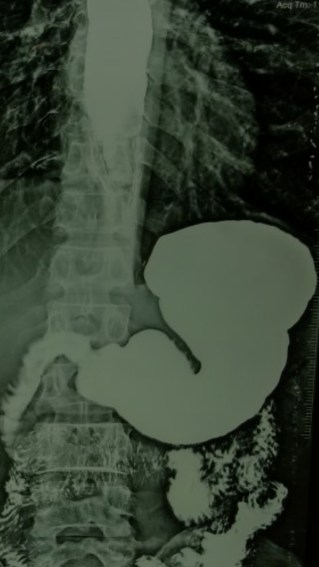

Now,we have every thing. Students read medicine in animated 3D class rooms , physicians get a deluge of body system data & images beamed straight into their ipad . One can perform complex interventions with ease in almost every organ or even replace it , if it doesn’t work .